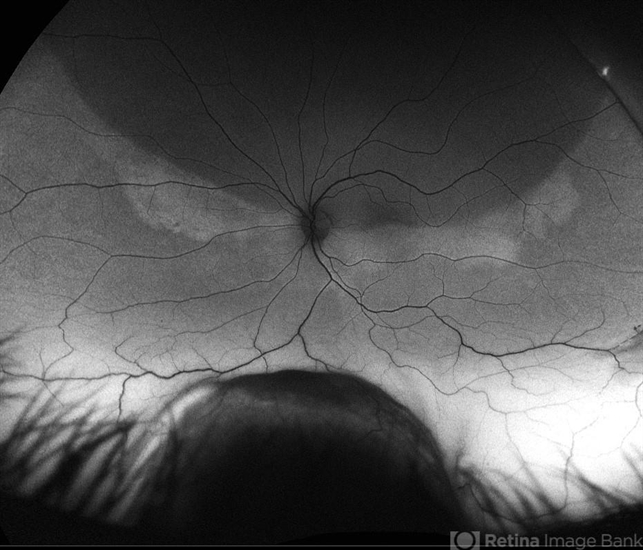

- brachytherapy, demarcation line, serous detachment, fundus autofluorescence (FAF), subretinal fluid

- 48 year old female 3 months s/p brachytherapy for choroidal melanoma. Persistent subretinal and increased subfoveal fluid. Will observe for now, will consider Ozurdex if no improvement. BCVA 20/80